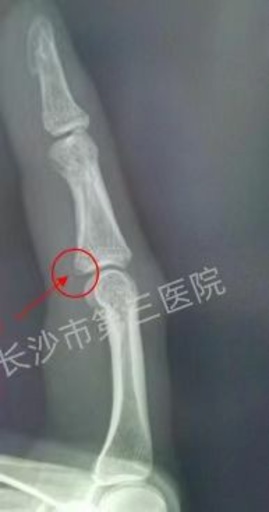

35歳の中国人女性 蚊をたたいてなんと骨折